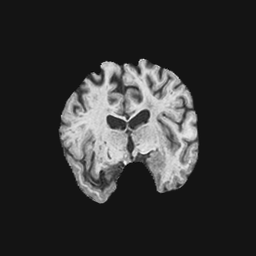

Exp. 1: Segmented adult brain data is used to evaluate our network’s regression performance with known ground truth . 85 brains from the ADNI data set[1] were randomly selected; 70 brains for and 15 brains for . Fig. 2 shows an example slice of the ground truth and the reconstructed .

Each brain has been centered and re-sampled in a volume. Using the Fibonacci Sphere Sampling method, a density of 500 unique normals is chosen with 64 sampling planes spaced evenly apart on the Z-axis (giving a spacing of 4mm). This therefore yields a maximum of 32000 images per brain; 2.24M for the entire training set and 345K for the entire validation set. After pruning with little or no content, this figure drops to approximately 1.2M images for training and 254K for validation. Training took approximately 27hrs for 30 epochs.

Reconstructing from initialisation without SVR yields a PSNR of 23.7 1.09; with subsequent SVR the PSNR increases to 29.52.43 when tested on 15 randomly selected test volumes after four iterations of SVR.

0..5 Randomly selected illustrative inference results

Here we show for Exp. 1, Exp. 2, and Exp. 3 randomly selected examples of images that have been presented to the network (ground truth) compared to an image sampled at the predicted location.

In these experiments, we present a ground truth (GT) image to the network to estimate the respective transformation parameters needed to reorient the slice in its correct world co-ordinates. Using the transformation parameters, we generated a slice from the 3D atlas in the location where the network has predicted that slice should be (denoted as SVRNet).

The slices are compared side-by-side to give a visual representation of “where the slice really is” and “where the network thinks the slice is”.

0..5.1 Exp. 1:

Slices, extracted from a correctly registered and reconstructed 3D volume, from the testing data set are presented to the network. The predicted slice is extracted from the same volume, using parameters estimated by SVRNet as shown in Fig. 8 and 9.